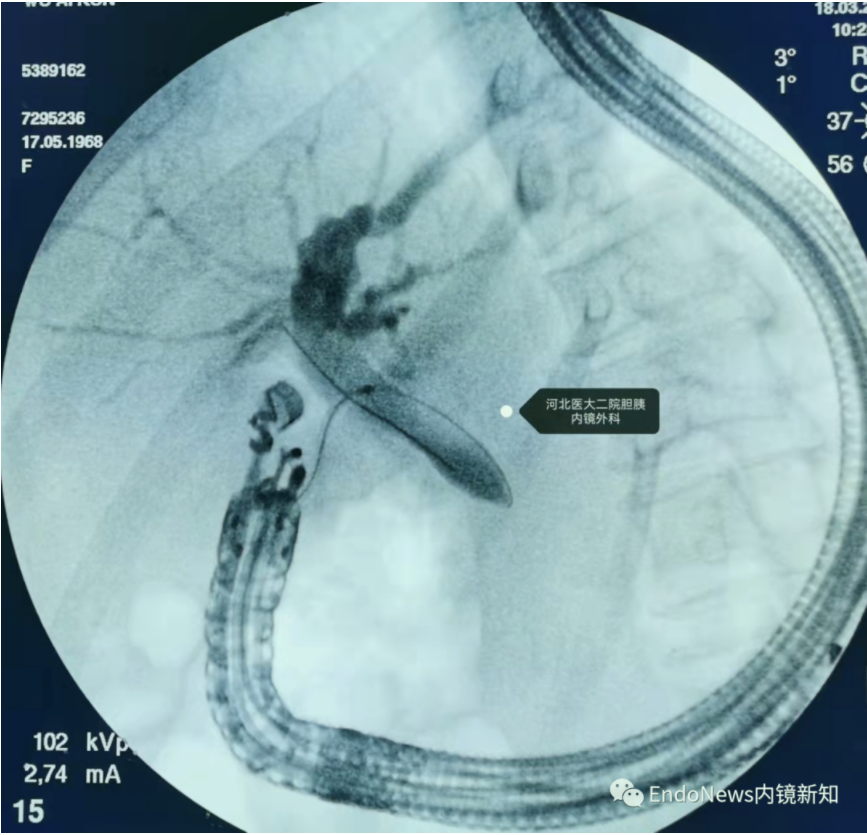

病例2:胆肠吻合口狭窄并右侧肝内胆管结石。

HGS造瘘,再碎石取石,置入双猪尾支架

在这个病例中,倘若是左肝管穿刺的第二段或第三段有结石,操作则更为困难,因此不同的病例还需要具体情况具体分析。